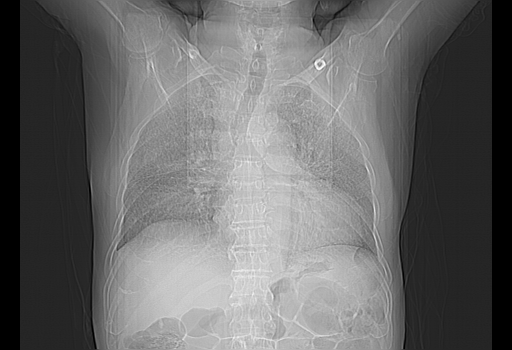

今天复查肺部CT,发现双肺广泛磨玻璃样改变。所以我把3月19日和5月9日相隔50天的肺部CT上传。请大家会诊。

2009年3月19日肺部CT片。

5月9日肺部CT(在4月27日齐鲁医院肺部CT描述部分肺组织磨玻璃样改变,12天后肺组织广泛磨玻璃样改变)